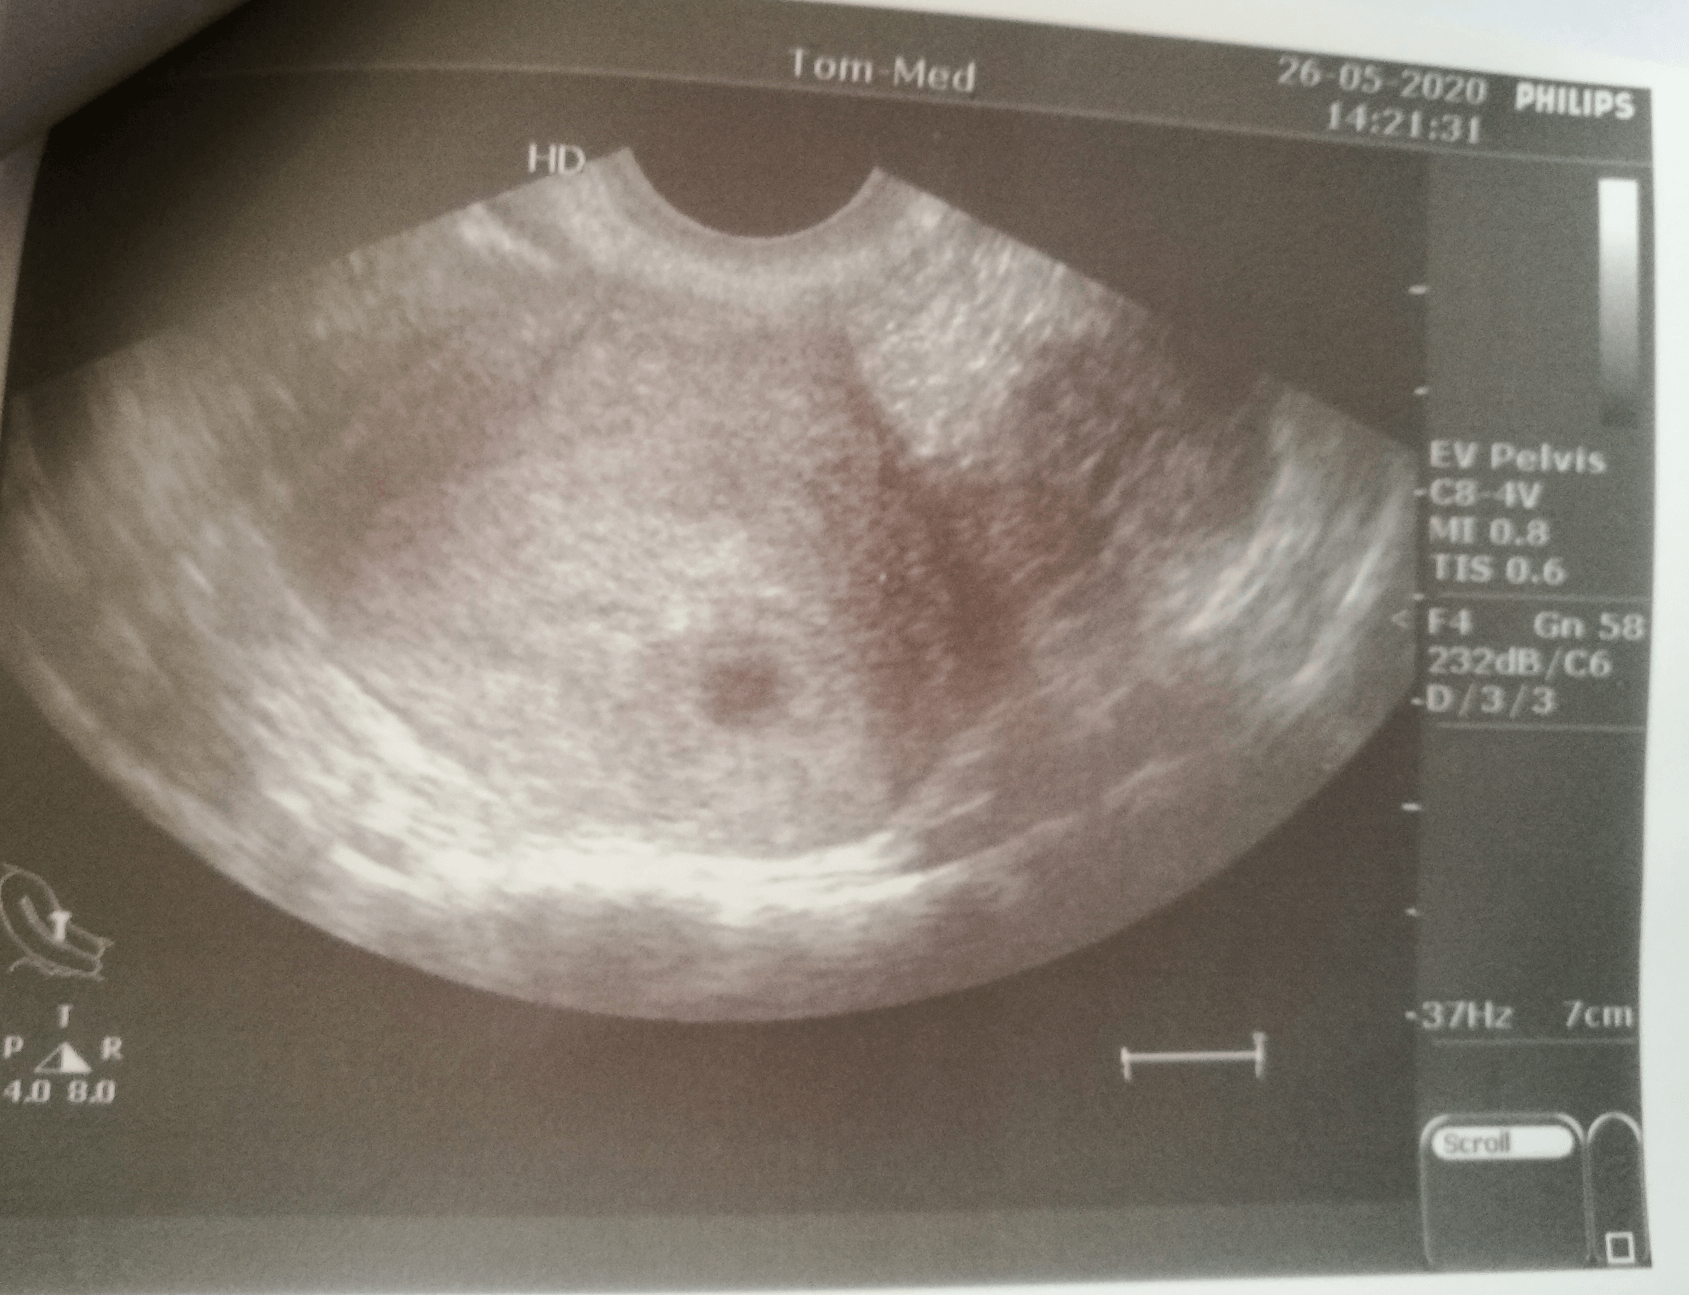

w zasadzie to nic nie wiem oprócz tego że ciąża jest i że ból piersi to dobry znak.... nawet lekarz nie liczył terminu powiedział tylko, że wg usg ciąża w 3cim tyg od zapłodnienia.

Zobacz załącznik 1124875

Zobacz załącznik 1124878